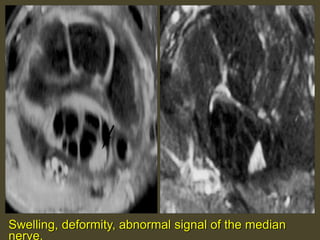

Swelling, deformity, abnormal signal of the median

nerve.